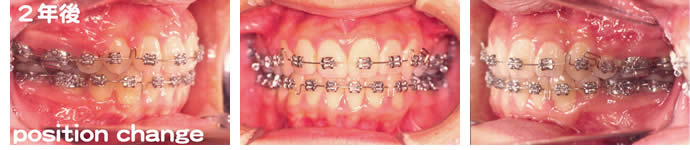

■2年後

抜歯したすき間が閉じ、上下の歯の正中のズレも小さくなっています。仕上げ前にもう一度歯のねじれをとっています。